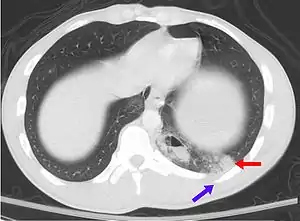

| A CT scan showing a pulmonary contusion (red arrow) accompanied by a rib fracture (purple arrow) | |

Computed tomography

Computed tomography (CT scanning) is a more sensitive test for pulmonary contusion,[6][33] and it can identify abdominal, chest, or other injuries that accompany the contusion.[38] In one study, chest X-ray detected pulmonary contusions in 16.3% of people with serious blunt trauma, while CT detected them in 31.2% of the same people.[45] Unlike X-ray, CT scanning can detect the contusion almost immediately after the injury.[43] However, in both X-ray and CT a contusion may become more visible over the first 24–48 hours after trauma as bleeding and edema into lung tissues progress.[46] CT scanning also helps determine the size of a contusion, which is useful in determining whether a patient needs mechanical ventilation; a larger volume of contused lung on CT scan is associated with an increased likelihood that ventilation will be needed.[43] CT scans also help differentiate between contusion and pulmonary hematoma, which may be difficult to tell apart otherwise.[47] However, pulmonary contusions that are visible on CT but not chest X-ray are usually not severe enough to affect outcome or treatment.[37]